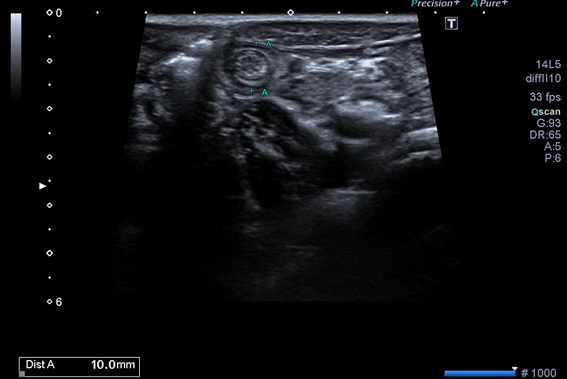

En la ecografía se hallan ganglios reactivos en fosa ilíaca derecha e invaginación ileo-ileal con imagen en diana, resuelta de forma espontánea mediante la compresión de la sonda ecográfica, confirmando el diagnóstico de adenitis mesentérica con invaginación intestinal secundaria.